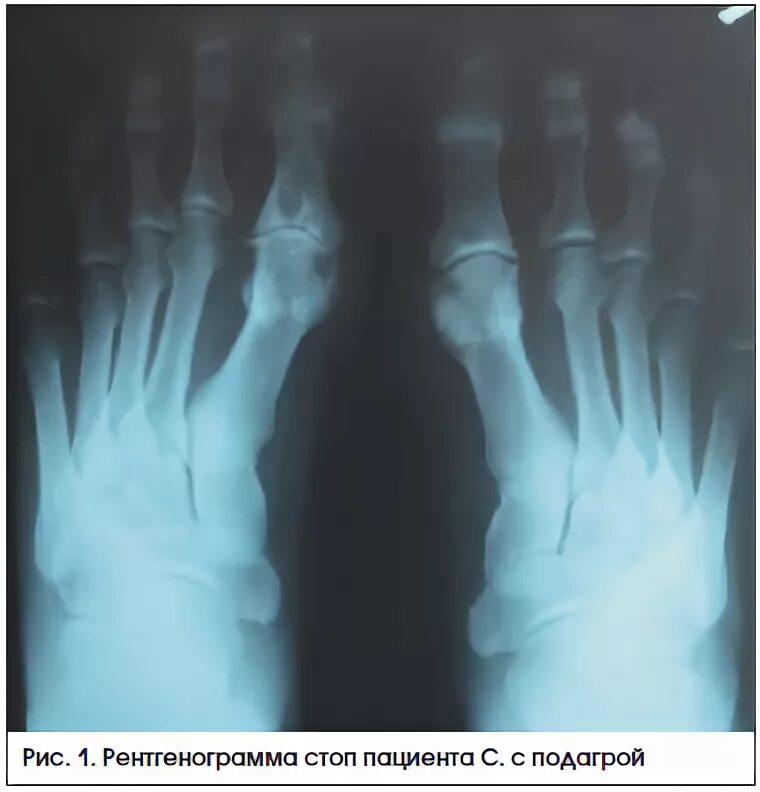

Артроз 1 степени плюснефалангового сустава стопы